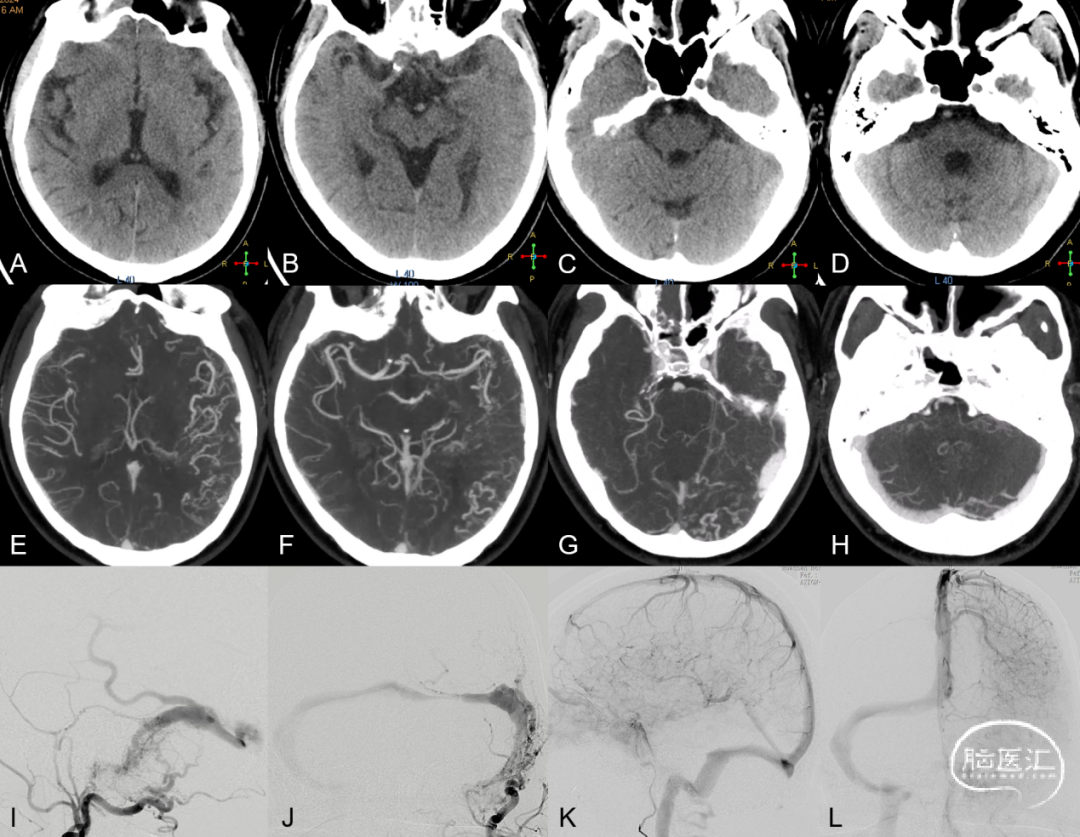

图5. CT平扫建左侧颞叶低密度影,脑回变浅,提示左侧颞叶肿胀,局部发生静脉性梗死 (A-D) ;左侧侧窦高密度 (C、D) ,提示静脉窦异常引流;CTA示左侧颞叶异常血管影,提示静脉引流瘀滞 (E-G),左侧横窦局部增宽及狭窄 (G、H) 。左侧颈外动脉造影证实左侧侧窦区硬脑膜动静脉瘘,左侧横窦狭窄,向对侧侧窦逆流,并向Labbe静脉逆流 (I、J) ;左侧颈内动脉造影示左侧大脑半球引流瘀滞,Labbe静脉不显影 (K、L) 。

图6. A-D弥散加权成像DWI显示左侧颞枕叶细胞毒性水肿;E-H T2WI成像显示左侧颞枕叶血管源性水肿;以上Labbe静脉相关脑区异常水肿征象提示同侧Labbe静脉引流异常。I、J左侧颈外动脉造影证实左侧侧窦区硬脑膜动静脉瘘,向Labbe静脉极其附属皮层静脉逆流;左侧颈内动脉造影示左侧Labbe静脉不显影,颞枕叶静脉引流瘀滞。